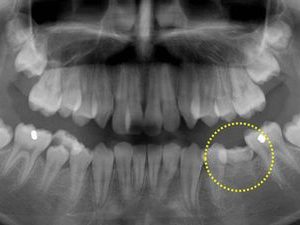

12歳の男の子、前歯がガタガタで出っ歯が気になるので矯正相談に来られました。レントゲン撮影したところ、下顎の第二小臼歯(黄色い丸で囲った部分)が先天的に欠損していて、乳歯がそのまま残っていることが判明しました。両隣りの ...